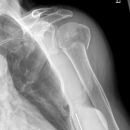

Hill-Sachs Läsion